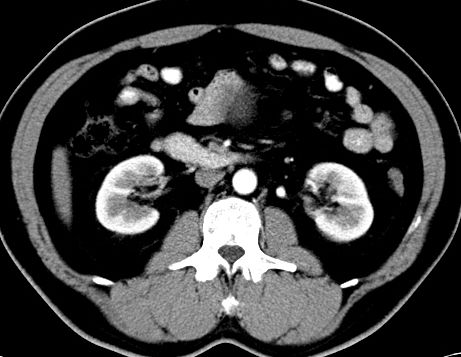

(腹腔)神经鞘瘤

男,48岁,间断性下腹不适1年。

手术探查

:距回盲部28厘米处肠系膜根部可见5*7cm左右包块,质中等硬度,活动度尚可,肝、胆、胰、脾肾未见明显异常。

病理

:(腹腔)

神经鞘瘤

,伴出血、坏死及囊性变,伴淋巴结反应性增生。

免疫组化结果

:sma(-), desmin(-), cd117(-), s-100(+++), nf(-),vimentin(+++).